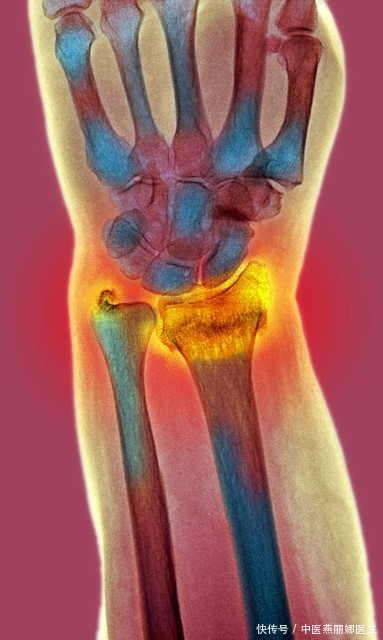

更年期女性,如何发现骨质疏松?该如何与之对抗?中医给出了真相

骨质疏松症